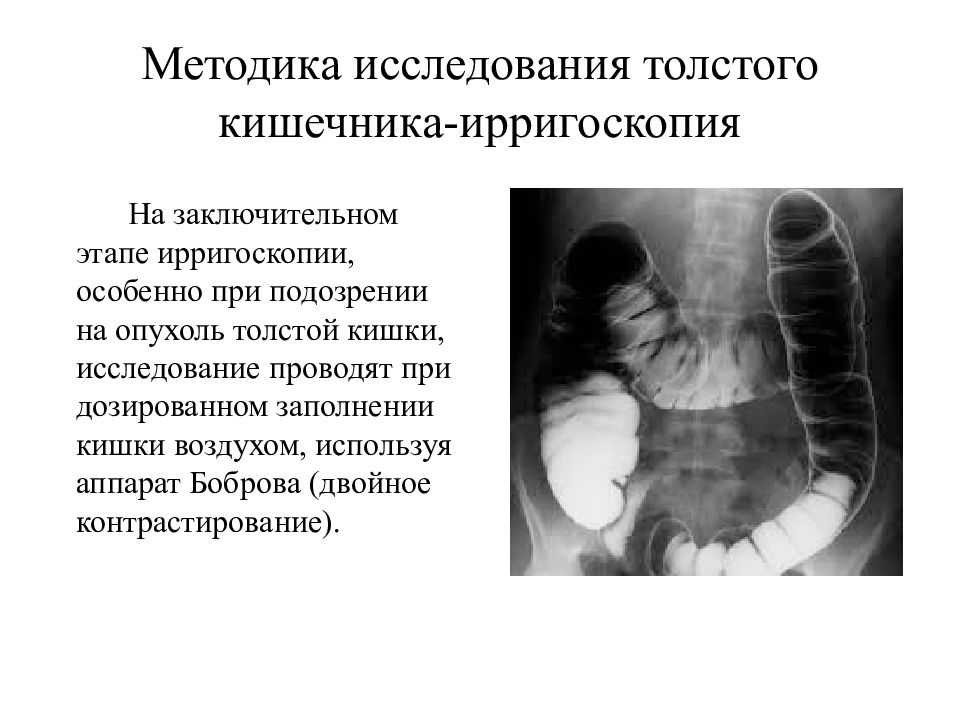

Рентгеноконтрастные Исследования Кишечника: Визуализация и Методики

Раздел: Иллюстрированный журнал